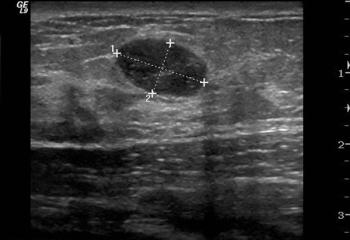

Breast cancer detection rates increase substantially when women at high risk and those with dense breasts undergo mammography and ultrasound annually, according to a study presented Wednesday at the 2009 RSNA meeting. MRI is an even more effective technique when used with mammography, but only for women who are at high risk for the condition.

Targeted breast ultrasound is less invasive and expensive than biopsy, as well as reduces anxiety over breast cancer screening.